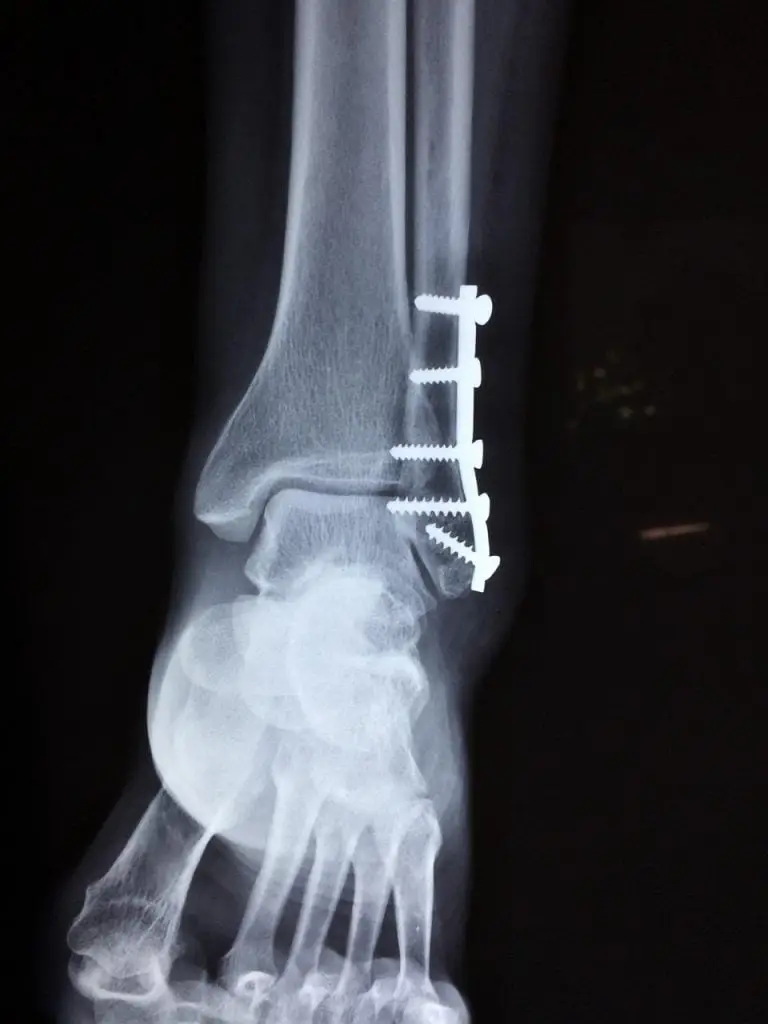

- Diagnostische beeldvorming: Geavanceerde beeldvormingstechnieken zoals röntgenfoto’s, MRI-scans en CT-scans worden gebruikt om orthopedische aandoeningen nauwkeurig te diagnosticeren en de beste behandelingsaanpak te bepalen.

- Orthopedische chirurgie: Indien nodig kunnen orthopedische chirurgen een breed scala aan operatieve procedures uitvoeren, waaronder gewrichtsvervangingen, arthroscopische ingrepen, botreconstructies en meer.

Voor patiënten met ernstigere of complexere orthopedische aandoeningen kunnen chirurgische ingrepen nodig zijn. Deze omvatten procedures zoals gewrichtsvervangingen, gewrichtsreconstructies, ligamentreparaties, fractuurfixaties en andere orthopedische operaties die worden uitgevoerd door ervaren orthopedisch chirurgen in Groningen.